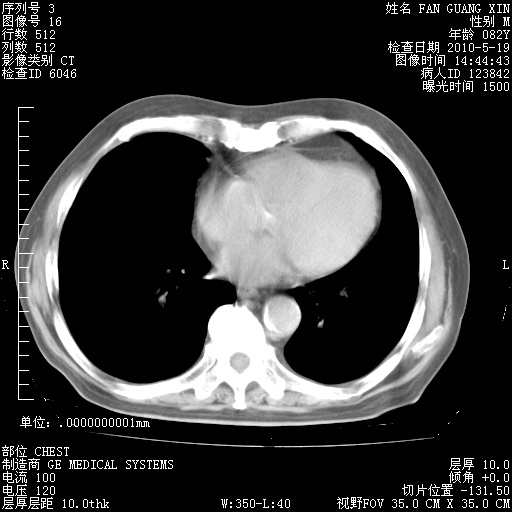

可改为口服强的松40-50mg/d治疗,若病情仍稳定,胸部阴影不再吸收可逐渐减量